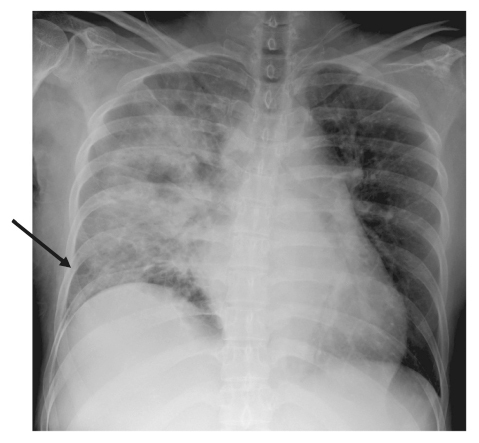

The incidence of Acinetobacter infections has increased in recent years. Acinetobacter infections are resistant to most antibiotics and can be found in hospitalized patients. Pregnancies complicated by severe sepsis or septic shock are associated with a higher rate of preterm labor and delivery, fetal infection, and operative delivery. This case report describes septic shock due to Acinetobacter lwoffii infection in the 31st week of gestation. A 47-year-old woman, with a gestation of 31 weeks and one day, presented with a fever, and signs of bacterial infection on laboratory tests. Although the patient was started on tazobactam/piperacillin, she went into septic shock, and was transferred to our hospital. Cesarean section was performed at a gestation of 31 weeks and 4 days because of severe maternal pneumonia and non-reassuring fetal status. A. lwoffii was detected in blood cultures collected at the previous hospital, and susceptibility to piperacillin and meropenem to A. lwoffii was confirmed. The pneumonia responded to antibiotic treatment and there were no findings of infection in the neonate. Maternal sepsis is an infrequent but important complication, causing significant maternal and fetal morbidity and fetal and neonatal mortality; therefore, early antibiotic therapy is required to improve the clinical outcome.

Abstract Image